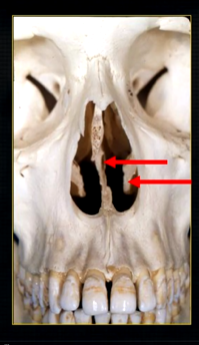

the upper jaw - the maxilla - what is circled in red?

the nasal cavity

what is seen here?

the nasal septum and the inferior nasal concha

what is the bottom arrow showing?

the floor of the nose - just above the apices of the upper anterior teeth